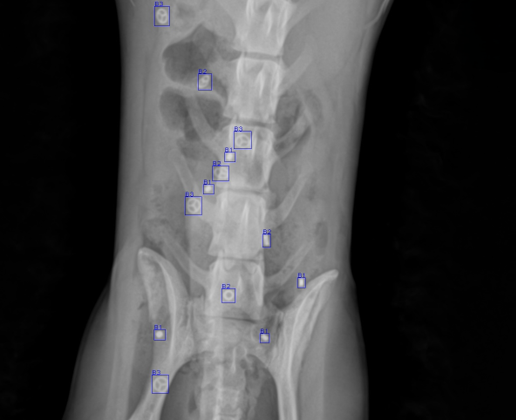

IntraMarX™ is a capsule-based diagnostic tool that delivers precise insights into colonic motility disorders such as chronic constipation, colonic inertia, and functional outlet delay. Each IntraMarX capsule contains 24 tiny radiopaque rings that become visible via abdominal X-ray after the capsule dissolves in the GI tract. Depending on the method used—Hinton (single capsule) or Metcalf (three capsule)—IntraMarX allows clinicians to assess overall and segmental transit times with a high degree of accuracy. This simple, well-tolerated test helps differentiate between global colonic hypomotility and rectosigmoid dysfunction, guiding appropriate treatment pathways.

Not all constipation is the same. In some patients, symptoms stem from impaired colonic muscle activity (colonic inertia), while others may struggle with outlet dysfunction at the rectum. IntraMarX plays a critical role in identifying the underlying cause of constipation, particularly in patients who fail to respond to first-line treatments like fiber, laxatives, or lifestyle changes. By mapping the movement of markers through the colon, physicians can more confidently diagnose slow-transit constipation or outlet delay, and tailor therapy—whether conservative, pharmacologic, or surgical.